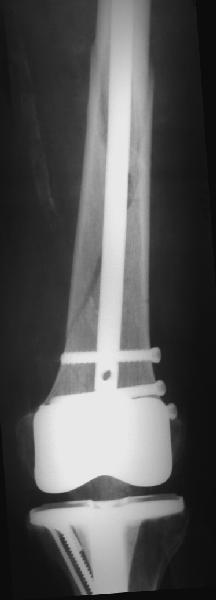

Уважаемые коллеги! 5.08.11 синтез бедренной кости пластиной LCP для дистального бедра.

Прошу совета. П-ка, 59 лет, автодорожная травма, перелом винтообразный н/3 левой бедренной кости. Планировалась закрытая репозиция и малоинвазивный доступ. по ходу операции пришлось немного открыть зону перелома для репозиции. Под контролем ЭОП вроде на столе смещение небольшое было и по оси терпимо. Сделали рентген контроль и получили вот картину. Еще обломилась головка кортикального винта. Синтез то стабильный. Только смещение не только не устранили, но кажется еще чуть больше стало (не могу) первичный снимок сделать). Склонен к ресинтезу и исправлению смещения из расширенного доступа. Как лучше выполнить репозицию? Какие можно использовать приемы репозиции? Спасибо.

Коллега,для адекватной оценки перелома необходимо предоставлять предоперационные и послеоперационные снимки в двух проекциях. Насколько возможно судить по маленькой картинке прямой проекции, на первый взгляд тут простой винтообразный перелом 32-А1. В таком случае самый стабильный вариант накостного остеосинтеза - это стягивающий винт перепендикулярно линии перелома и нейтрализирующая пластина. Особых показаний к малоинвазивному мостовидному остеосинтезу нет, т.к. при нем ниже стабильность фиксации, и все микродвижения сконтрентрируются в сравнительно небольшой зоне перелома, что приведет к большим смещающим силам. Однако, если присмотрется, на снимке видно что линия перелома продолжается до начала медиального мыщелка, поэтому скорее всего это клиновидным перелом со спиральным клином 32-В1. В таких случаях возможно выполнение мостовидного синтеза, однако в данном случае дистальная часть клина не смещена относительно дистального конца бедренной кости, таким образом, мне кажется, биомеханически ситуация представляет собой среднее между А1 и чистым В1. Смещающие усилия концентрируются в проксимальной части перелома, тогда как в дистальной несмещенной части они минимальны, в т.ч. из-за интактной надкостницы. Поэтому в данном конкретном случае, при невозможности выполнения интрамедуллярного блокирующего остеосинтеза, я бы выполнил остеосинтез с двумя стягивающими винтами (с рассверливанием ближнего кортикала сверлом большего диаметра) и нейтрализирующего остеосинтеза пластиной. Причем пластина могла бы быть даже обычная.

На представленных снимках, репозиции нет, есть вальгус. Полагаю фиксация не стабильна. Перелом может и срастется, но это будет долго и без нагрузки. Если бы была использована обычная пластина, можно было бы попробовать малоинвазивно подтянуть дистальный отломок и зафиксиривовать парой винтов. Однако примененные блокирующие винты не позволят этого сделать. Как вариант, возможно открытся снизу удалить винты, сделать небольшой доступ в зоне перелома (или попробовать закрыто) ввести 1-2 винта для фиксации клина, и перепровести блокирующие дистальные винты. В любом случае, стабильность при любом из этих вариантов будет заведомо ниже чем при стягивающих винтах + нейтрализирующей пластине. Удачи.

Мы в последние 4-5 лет переломы дистального отдела бедренной кости синтезируем преимущественно малоинвазивно пластинами с неплохими результатами.

Для принятия решения в данном случае желательно переделать прямую проекцию на длинной кассете с захватом коленного сустава - четче оценить оси, остаточные и качество фиксации; однако и имеющийся снимок не вызывает ощущения катастрофы - вполне неплохо должно срастаться.

Склоняюсь к тому, что лучше переделать. Сломанный винт в зоне перелома с большой долей вероятности является распоркой, что не будет способствовать сращению, особенно учитывая недостаточную стабильность. Действительно, чтобы удалить винт придется временно снять конструкцию. Я бы все-таки ввел для фиксации клина хотя бы 1 винт проксимально, можно не через пластину.